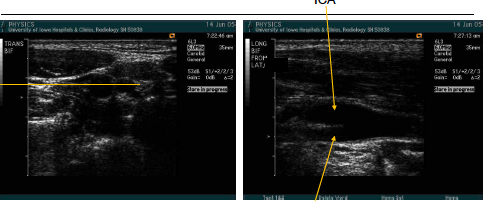

what are the arrows pointed to? what approach is being used?

trans CCA prox

what are teh arrows pointing to here? what image is being taken?

trans CCA mid

what image is being collected? what approach?

trans bulb from lateral approach

what image is being taken here? from what approach? wha can be noted about the window?

tran bulb from ant window.

less of the SCM muscle is used as the window

this image is showing…

trans bifurcation (continue to image sup as far as possible) lateral approach